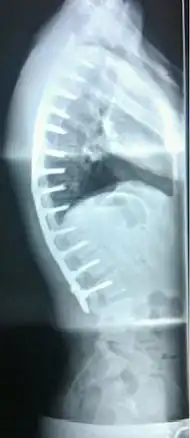

Scheuermann's disease

| Scheuermann's disease on lateral Xray of the T spine | |

In severe or extreme cases, patients may be treated through an extensive surgical procedure in an effort to prevent the disease from worsening or harming the body. The skeletal deformity caused by Scheuermann's disease can be corrected or partially corrected with surgical procedures, almost all of which include multi-level spinal fusion and hardware instrumentation, i.e., rods, pedicle screws, etc. It is important to realize the surgery aims to reduce pain, and not cosmetic defect. As always, surgical intervention should be used as a last resort once conservative treatment fails or the patient's health is in imminent danger as any surgical procedure is not without risk. However, the chances of complication are relatively low, and the surgeries are often successful.

There are two primary surgical techniques to correct kyphosis: posterior-only fusion and anterior/posterior fusion. While debate lingers over which surgical approach is optimal, several studies published since 2018 suggest treatment trends are favoring posterior-only fusion.[17][18][19]

The classic surgical procedure entails entering two titanium rods, each roughly 1.5 feet (0.46 m) long (depending on the size of the kyphosis) into the back on either side of the spine. Eight titanium screws and hardware are drilled through the bone to secure the rods onto either side of the spine. On the internal-facing side of the spine, ligaments (which can be too short, pulling the spine into its abnormal shape) must be surgically cut or released, not only stopping part of the cause of the kyphosis, but also allowing the titanium rods to pull the spine into a more natural position. The damaged discs between the troubled vertebrae (wedged vertebrae) are normally removed and replaced with bone grafting from the hip or other parts of the vertebrae, which once healed or "fused" will solidify. The titanium instrumentation holds everything in place during healing. The patient can expect to remain in hospital for a minimum of a week, and possibly longer. They may then be required to wear a brace for several months more to ensure the spine heals appropriately. The titanium instrumentation may stay in the body permanently, or be removed years later. Patients who have undergone such surgery may need physical therapy to manage pain and mobility. Recovery can be prolonged: typically patients are not allowed to lift anything above 5–10 pounds (2.3–4.5 kg) for 6 months to 1 year, and many are out of work for 3 to 6 months. However, once the fusion is solidified, most patients can return to their usual lifestyle within 1–2 years.